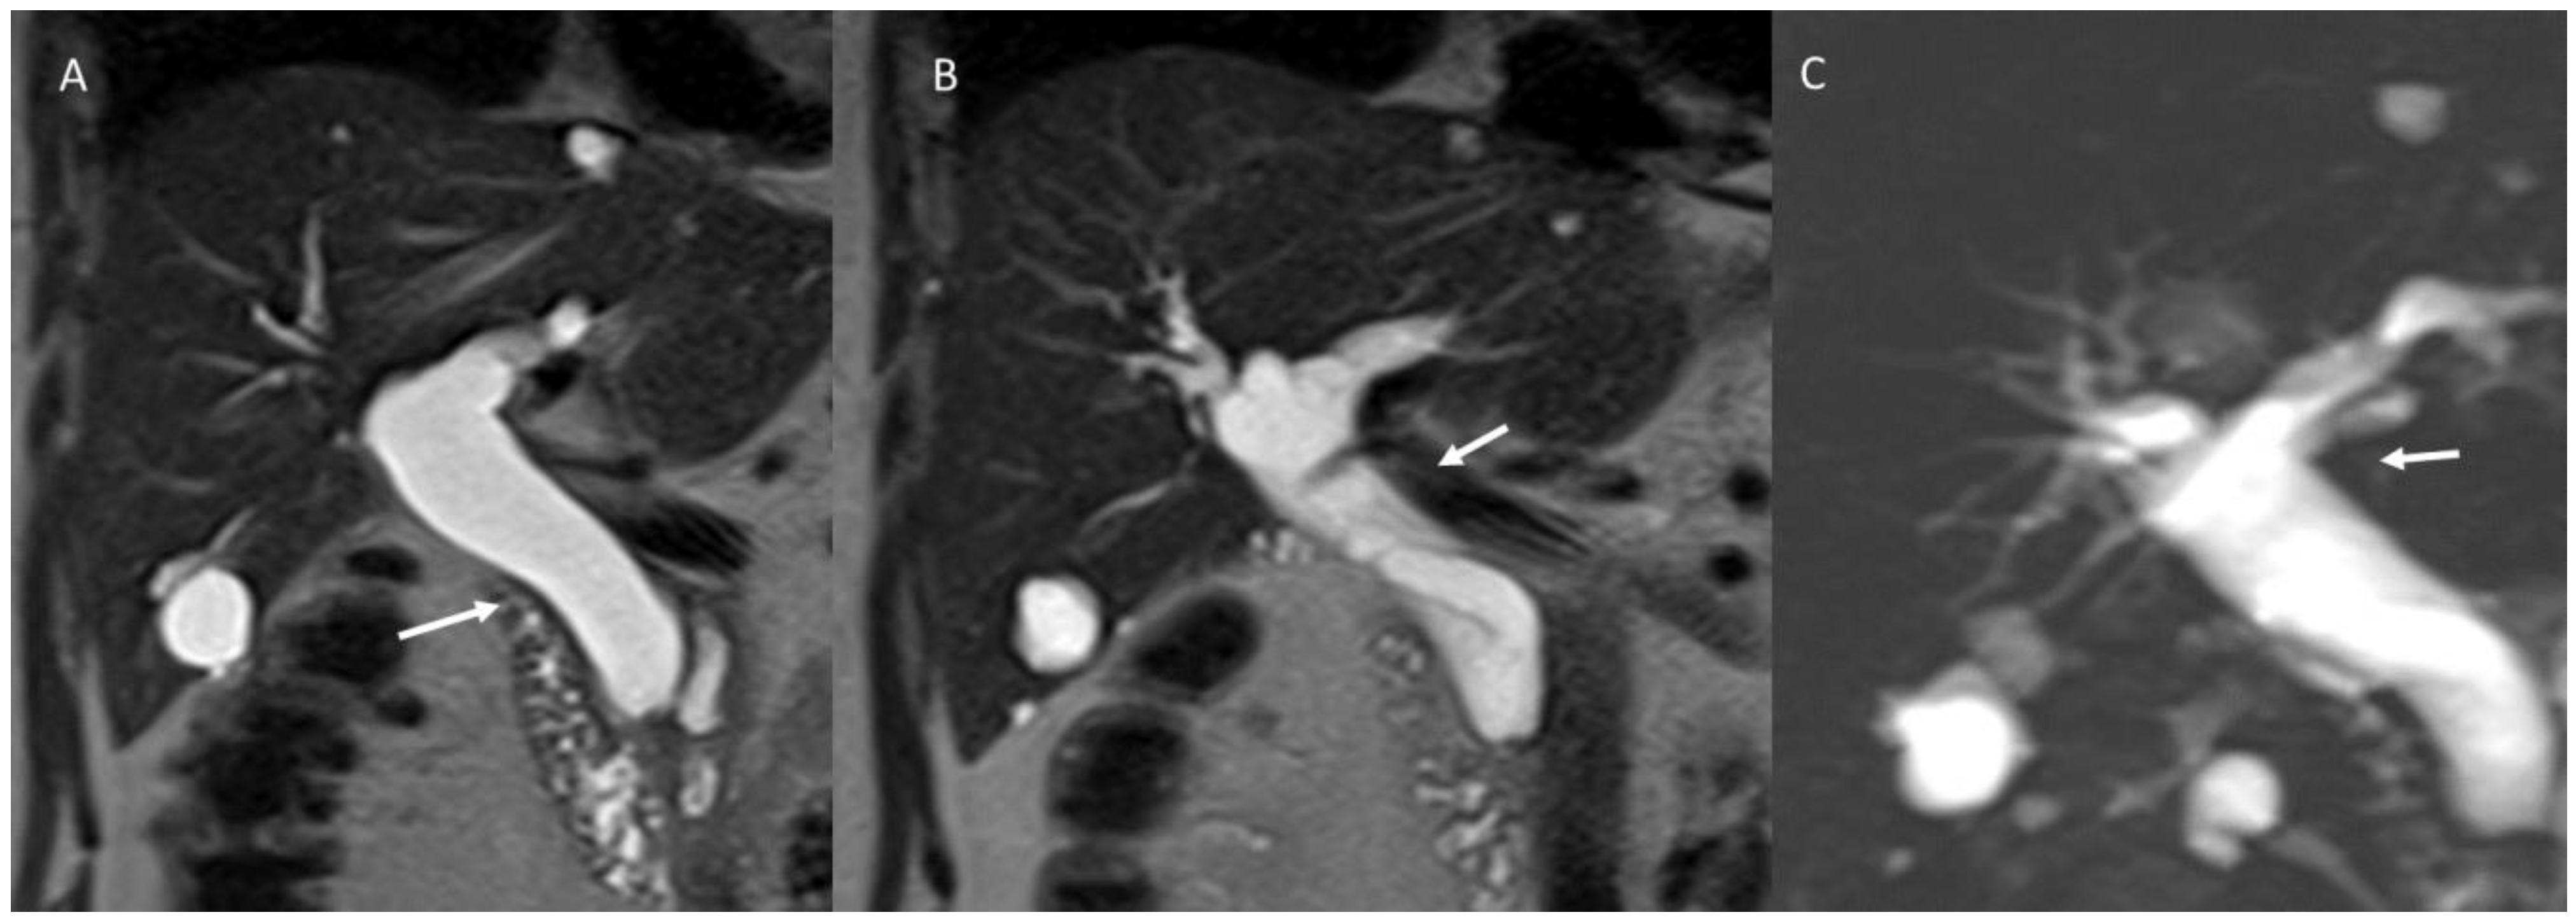

6.2. Intraductal Papillary Neoplasia of the Bile Duct

6.3. Intraductal Tubulopapillary Neoplasms of the Bile Duct